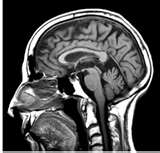

Nel 2010, 50 milioni di statunitensi hanno sofferto di problemi mentali

Secondo un rapporto governativo, un adulto su cinque negli Stati Uniti, o se preferite quasi 50 milioni di persone, ha sofferto malattie mentali durante l’anno 2010, con donne e giovani adulti che ne soffrono in maniera sproporzionata.

Il sondaggio condotto dalla Substance Abuse e Mental Health Services Administration ha scoperto che le donne avevano maggiori probabilità rispetto agli uomini (23% contro 16,8%) di aver vissuto una malattia mentale, mentre il tasso di malattie mentali tra le persone dai 18 ai 25 è raddoppiato rispetto a quello delle persone di età superiore ai 50.

L’indagine ha rilevato che il 5% degli adulti americani intervistate nel 2010 aveva subito una grave malattia mentale nel corso dell’anno passato che ha sostanzialmente interferito con la loro vita. Secondo il rapporto, circa 8,7 milioni di americani adulti ha avuto gravi pensieri rivolti al suicidio l’anno scorso, con 2,5 milioni di individui che hanno addiritturaelaborato piani suicidi e 1,1 milioni che hanno tentato di togliersi la vita.